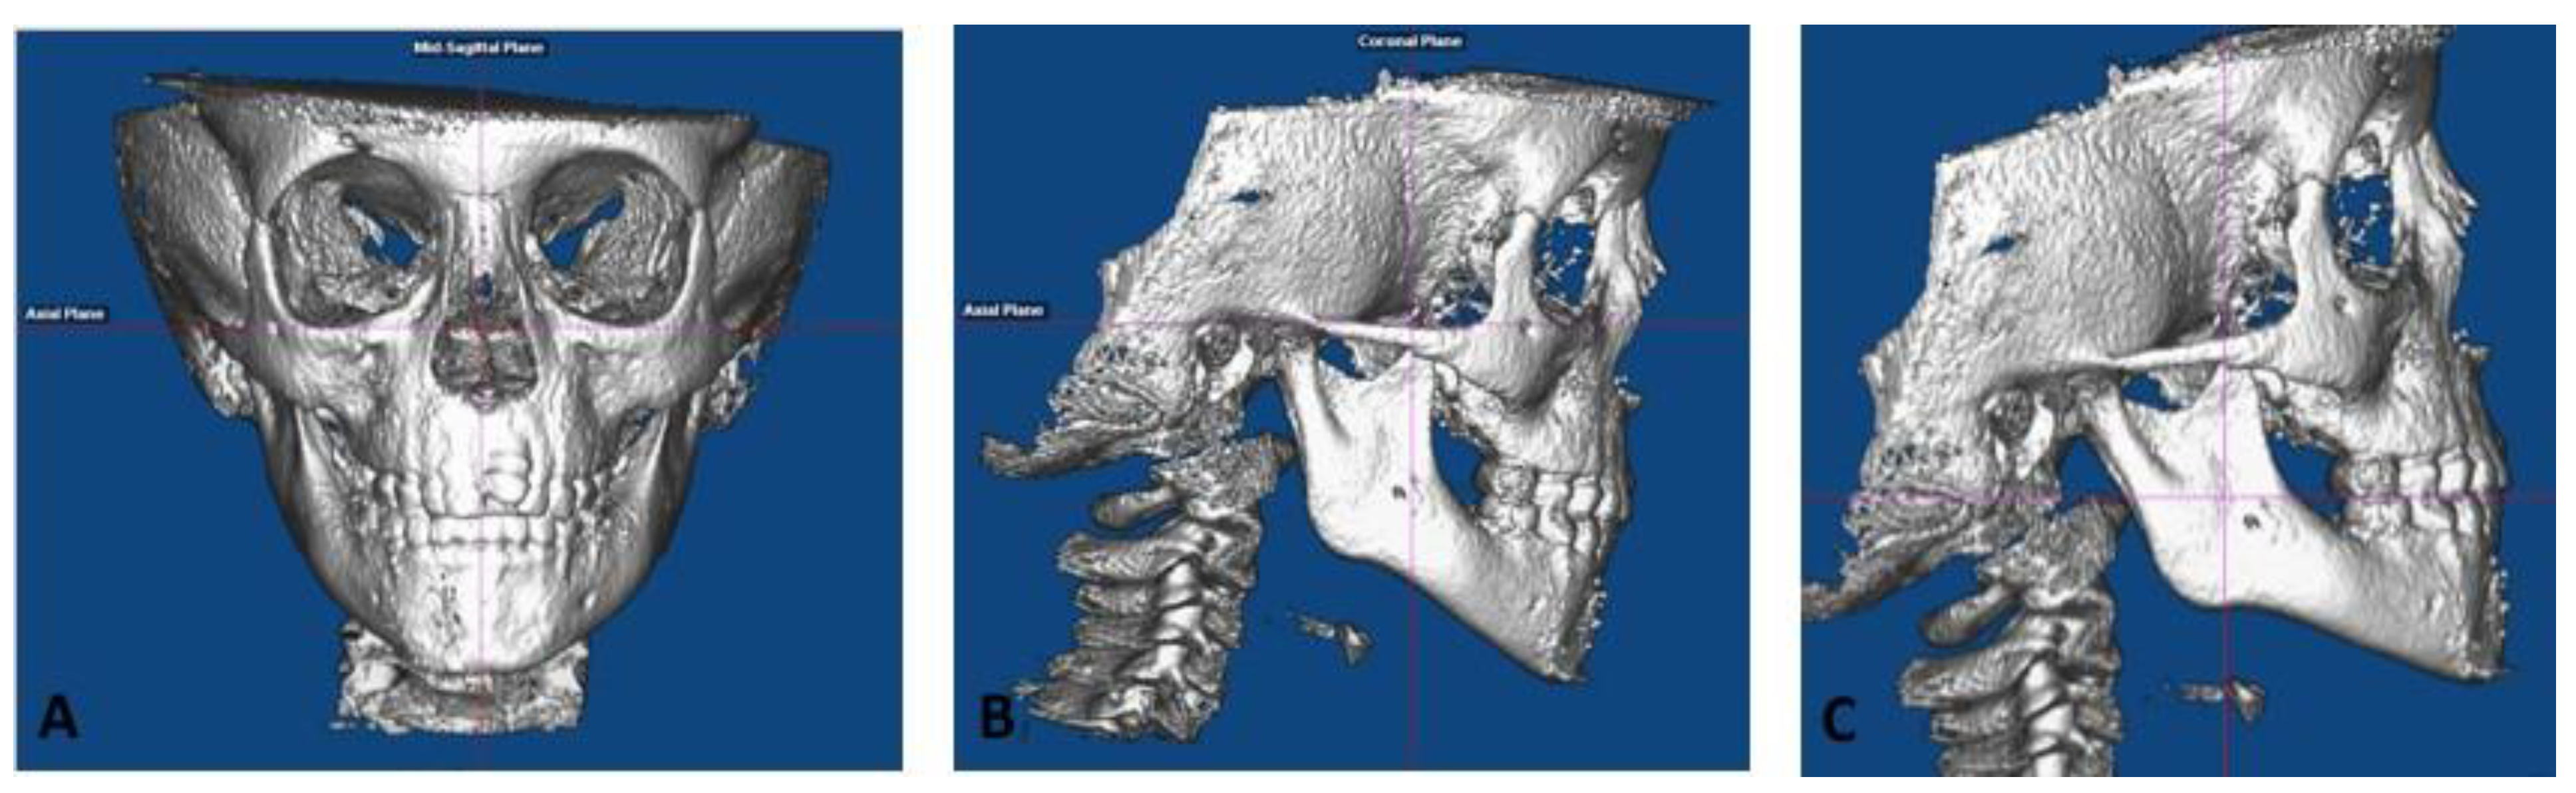

- Roll: The cranium was oriented such that a midline could be drawn through the midpoint of the frontonasal suture and base of the nose and is parallel to the true vertical (Figure 1A). In addition, a true horizontal line goes through the most inferior aspect of the orbits.

- Yaw: The cranium was oriented to achieve the best symmetry of the cranium, zygomatic, and maxillary structures on either side of the midline (Figure 1A).

- Pitch: For measurements on the non-tooth-bearing, skeletal features of the face, the cranium was oriented such that the Frankfort horizontal plane was parallel to the true horizontal plane (Figure 1B). For measurements on the tooth-bearing, dentoalveolar areas, the cranium was oriented such that the functional occlusal plane was parallel to the true horizontal plane (Figure 1C).